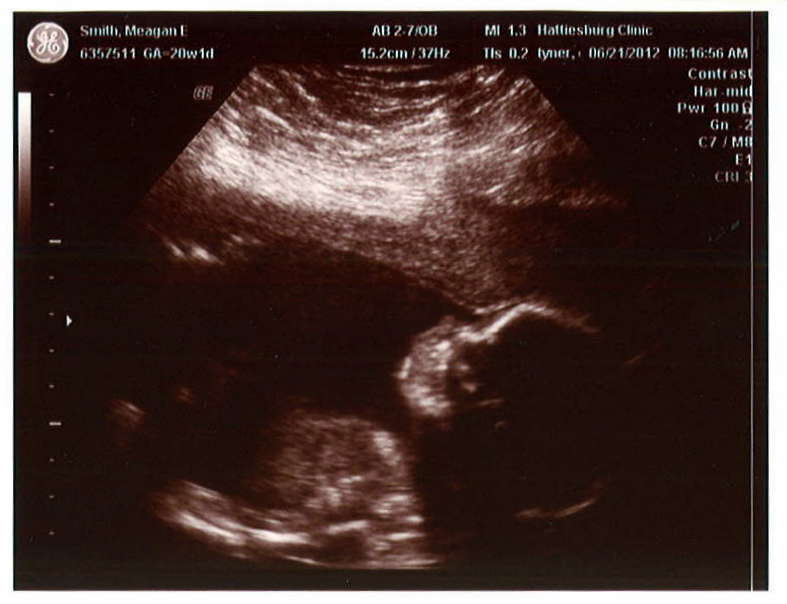

By the way, our baby is a BOY and his name is Clay.

In 13-ish weeks, Baby Clay will be outside of my belly and motherhood will commence. I’m very happy/scared witless about this. I tell myself that it’s a good thing that I’m scared, that I wouldn’t be a good mom if I didn’t care enough about my child to be apprehensive. I don’t know if this is true, but it’s currently how I get by. I’ve read lots of books and advice online, and I am sure that instinct will take over. Oh! And Husband and I have raised two dogs, so surely, combining these things will prepare me for…you know…not harming him. Here’s the deal: There will soon be this tiny, innocent, precious life whose survival will depend on me. That’s a lot to take in. And I love him so already, and if anything/one were to hurt him, most particularly if I were to hurt him, I would be beyond devastated. Woah, that got heavy. Let’s move on.